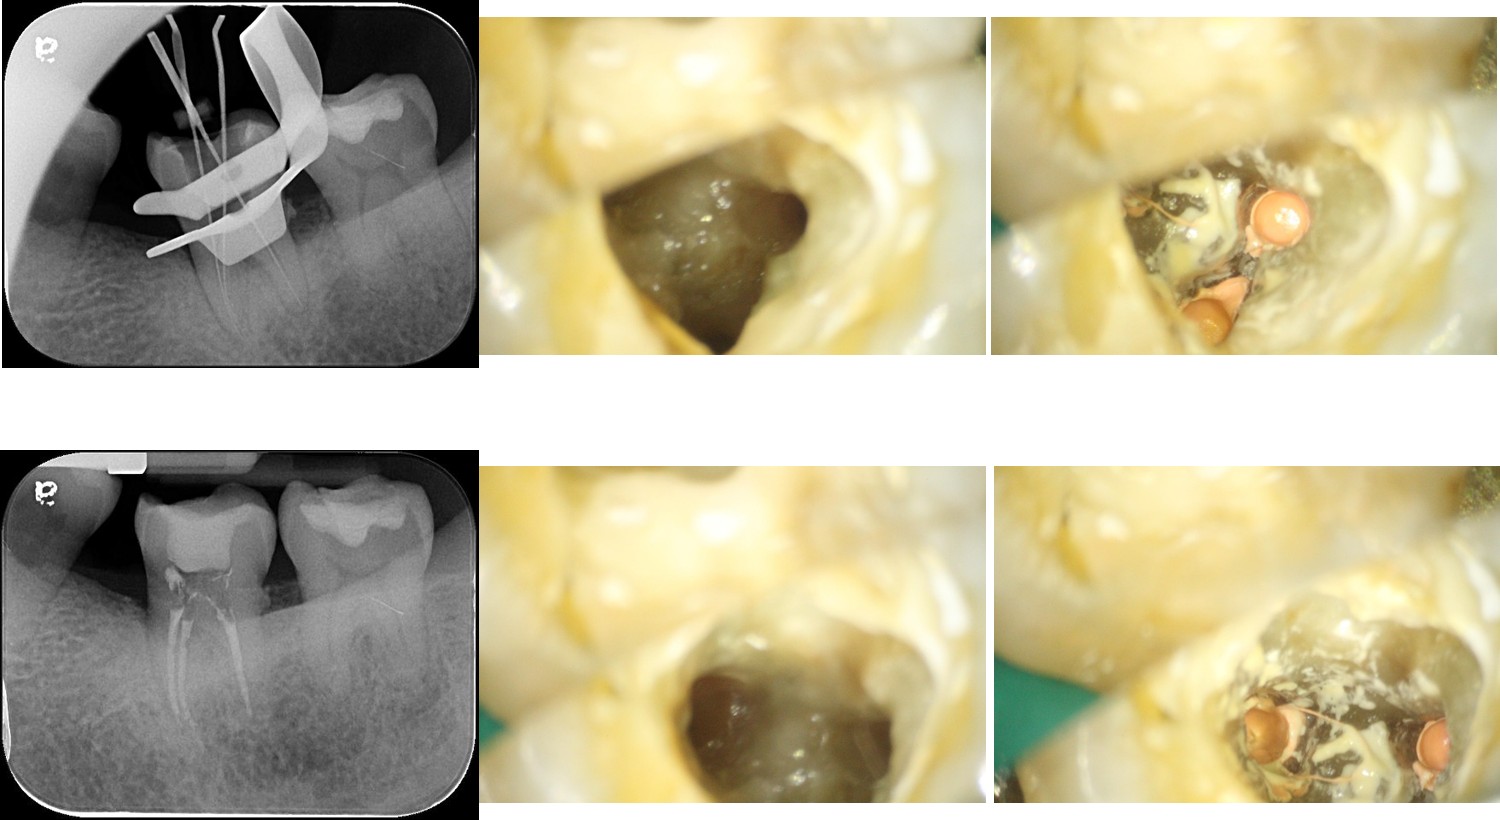

#37-顯微根管治療

根管治療操作範圍極為狹小, 過程中可能遭遇異物堵塞、狹窄鈣化、穿孔、分岔、帶狀根管、或前次治 療發生特殊困難等。 牙科專用顯微鏡可提供照明及放大,搭配專用超音波等特殊器械,可協助牙髓病專科醫師解 決 上述困難, 增進清潔根管效率;保留更多的齒質,增加保留牙齒 的機率。另外亦可協助牙醫師進行裂齒之診斷。因為深度齲齒或裂齒而曾經進行根管治療的牙齒,牙齒有了一定程度的缺損,缺損越大,牙齒裂掉的風險就越高,因此選擇適合的復形物來保護脆弱的牙齒,是非常重要的,齒質的缺損程度,將會決定牙齒適合以哪一種方式來復形。